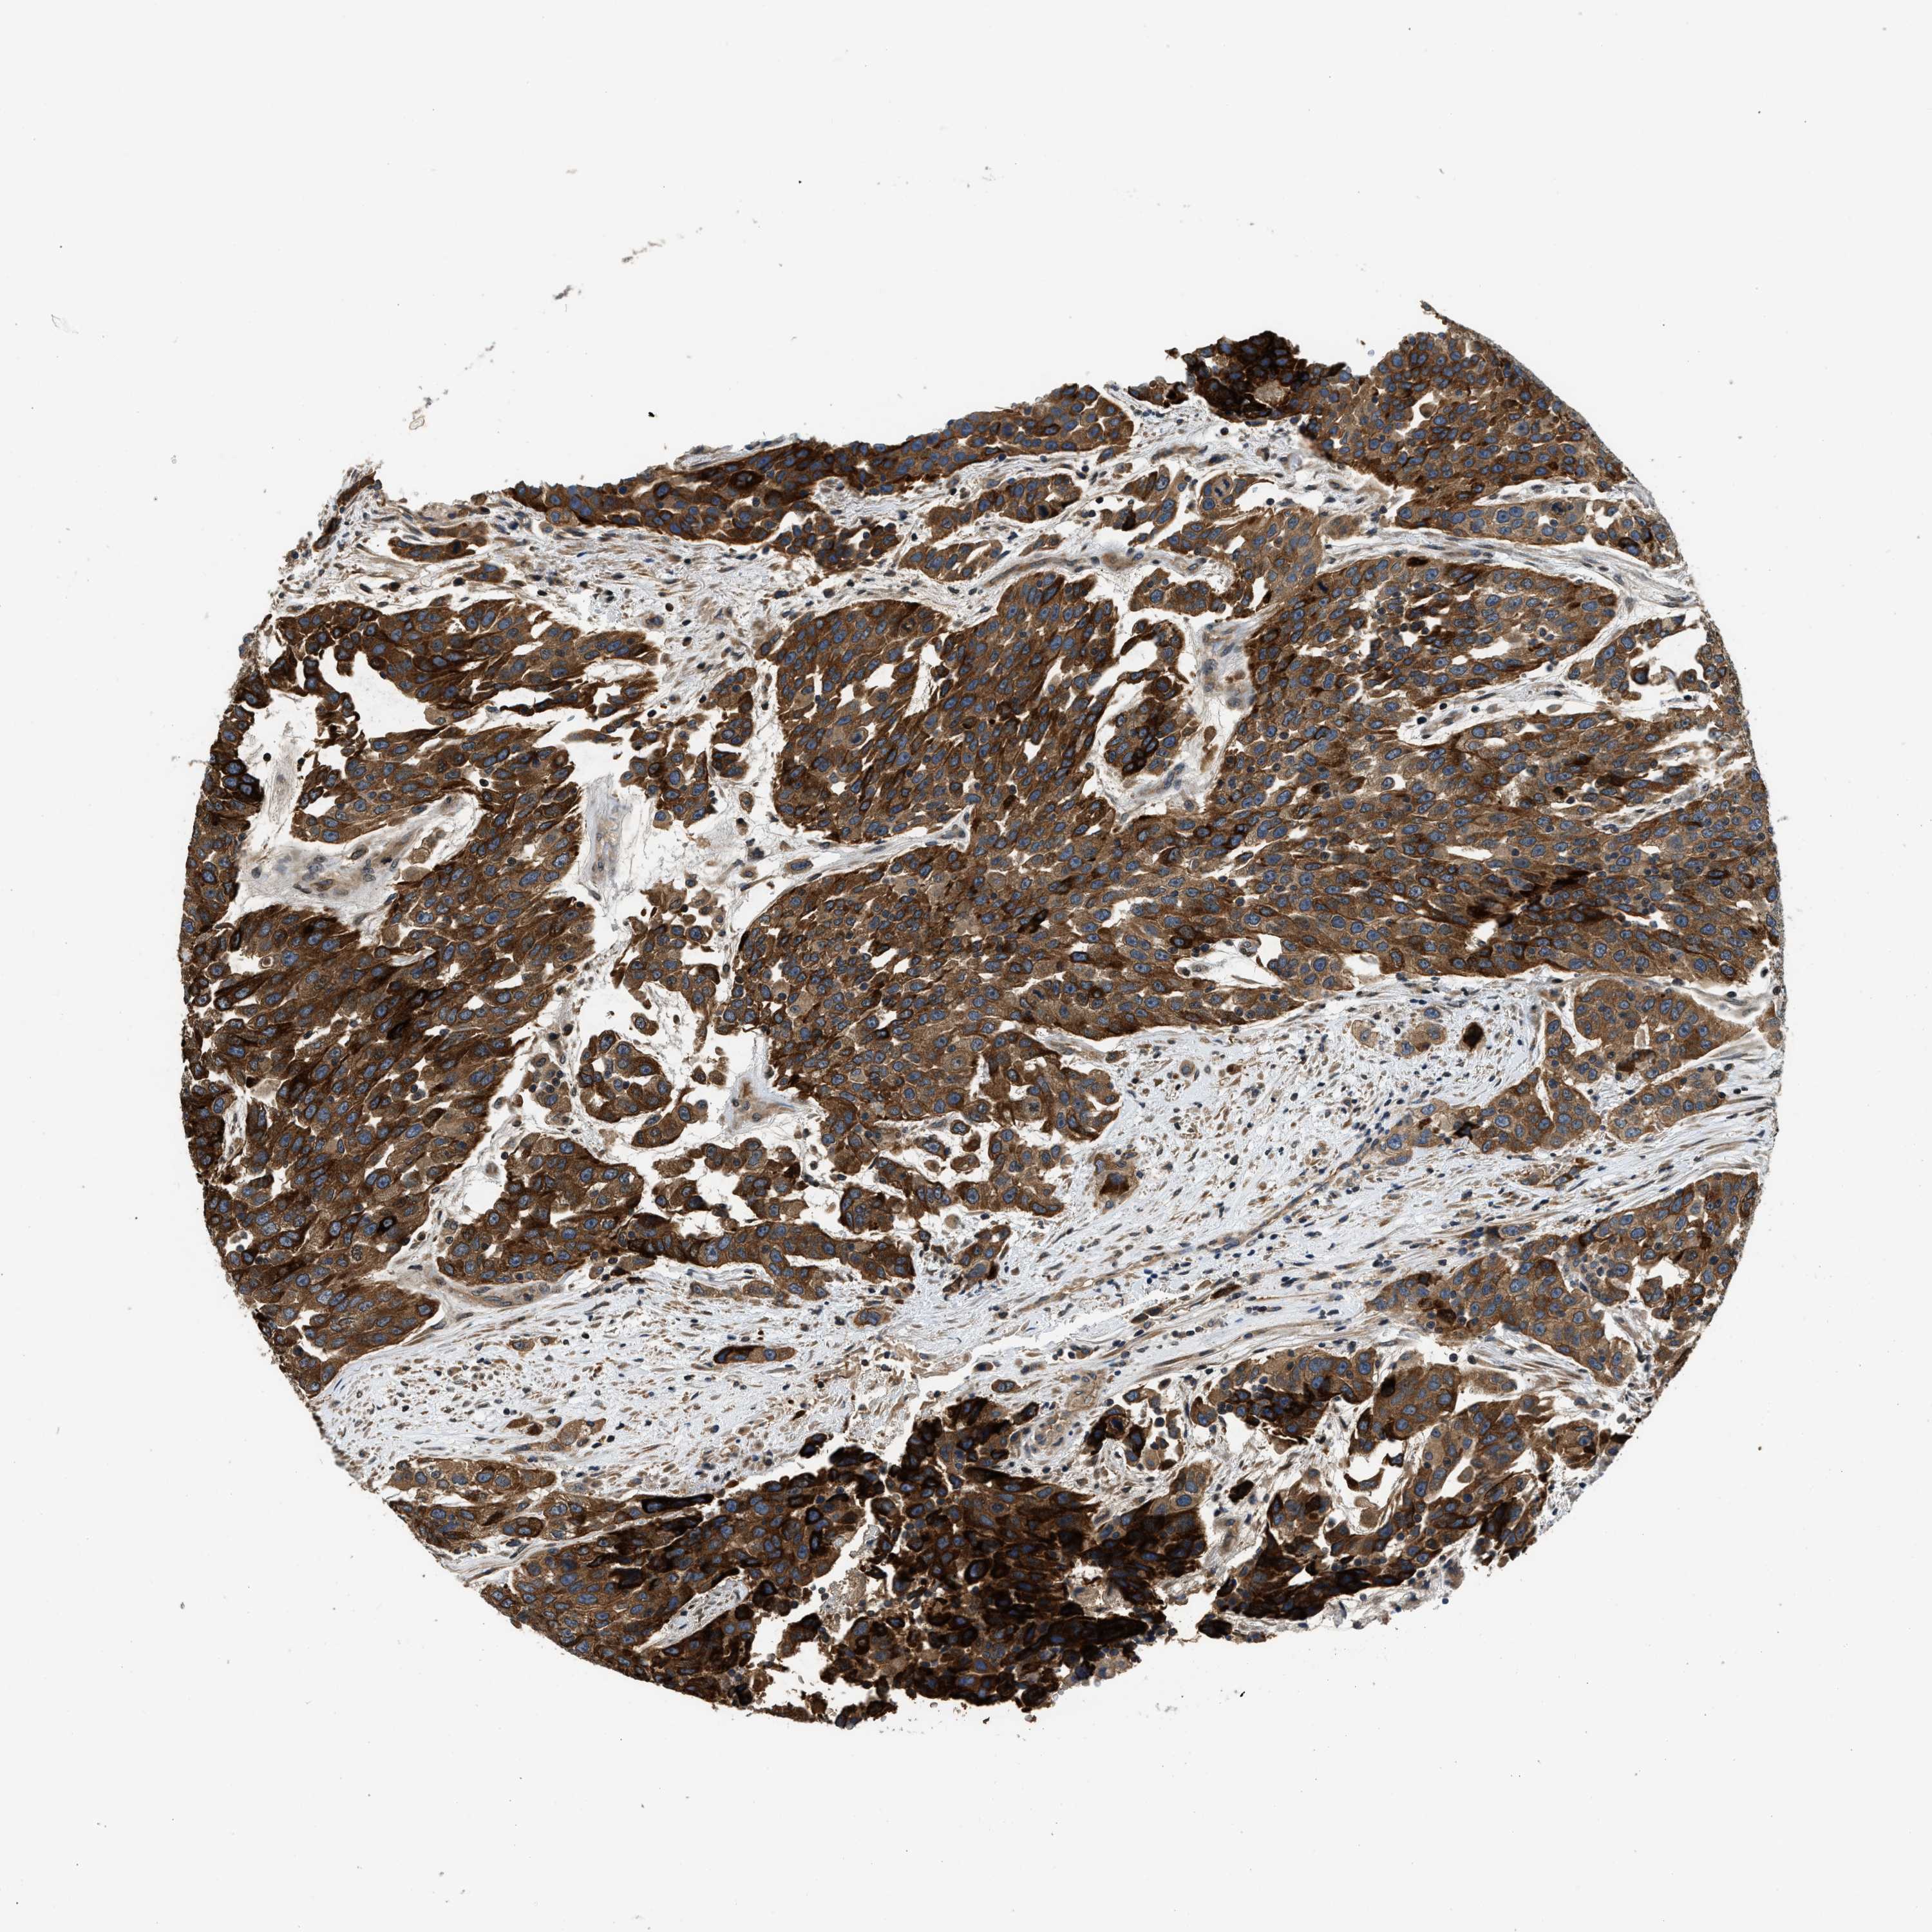

UROTHELIAL CANCER - Protein expressioni

A mouse-over function shows sample information and annotation data. Click on an image to view it in a full screen mode. Samples can be filtered based on level of antibody staining by selecting one or several of the following categories: high, medium, low and not detected. The assay and annotation is described here.

Antibody stainingi

Antibody staining in the annotated cell types in the current human tissue is reported as not detected, low, medium, or high, based on conventional immunohistochemistry profiling in selected tissues. This score is based on the combination of the staining intensity and fraction of stained cells.

Each image is clickable and will lead to virtual microscopy that enables deeper exploration of all samples and also displays staining intensity scores, fraction scores and subcellular localization as well as patient and tissue information for each sample.

Antibody HPA003539

Antibody CAB018374

Staining

High

Medium

Low

Not detected

Intensity

Strong

Moderate

Weak

Negative

Quantity

>75%

75%-25%

<25%

None

Location

Nuclear

Cytoplasmic/membranous

Cytoplasmic/membranous,nuclear

Urothelial carcinoma, High grade

Urothelial carcinoma, Low grade